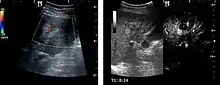

Hepatocellular carcinoma (HCC)

It is the most common liver malignancy. It develops secondary to cirrhosis therefore, ultrasound examination every 6 months combined with alpha fetoprotein (AFP) determination is an effective method for early detection and treatment monitoring for this type of tumor . Clinically, HCC overlaps with advanced liver cirrhosis (long evolution, repeated vascular and parenchymal decompensation, sometimes bleeding due to variceal leakage) in addition to accelerated weight loss in the recent past and lack of appetite.

HCC appearance on 2D ultrasound is that of a solid tumor, with imprecise delineation, with heterogeneous structure, uni- or multilocular (encephaloid form). An "infiltrative" type is also described which is difficult to discriminate from liver nodular reconstruction in cirrhosis. Typically HCC invades liver vessels, primarily the portal veins but also the hepatic veins . Doppler examination detects a high speed arterial flow and low impedance index (correlated with described changes in tumor angiogenesis). The spatial distribution of the vessels is irregular, disordered. CEUS examination shows hyperenhancement of the lesion during the arterial phase. During the portal venous phase there is a specific "wash out" of ultrasound contrast agent (UCA) and the tumor appears hypoechoic during the late phase. Poorly differentiated tumors may have a stronger wash out leading to an isoechoic appearance to the liver parenchyma during portal venous phase. This appearance was found in approx. 30% of cases. The described changes have diagnostic value in liver nodules larger than 2 cm.